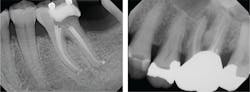

Because endodontics necessitates capturing a fair number of radiographs, endodontists appreciate 2-D digital imaging because it requires a lower amount of radiation than traditional film radiography. Such is the case with my DEXIS system (figure 2). Studies have shown that capturing one view of a tooth garners only a limited percentage of information, but both a straight-on view and an angled view results in a greater amount of details. Also, in a digital format, quick access to the data results in more efficient use of time.

During endodontic treatment, I may need a “check” radiograph to see if I am in the proper length for a root canal, or if I am in the proper orientation for access. My digital system allows me to quickly capture an image. For these check radiographs, DEXIS provides sensor holders in the shape of paddles that allow the rubber dam to stay on while capturing an image and not violating sterilization protocol.